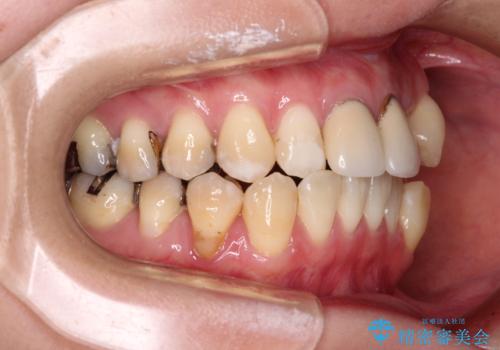

- 前歯のデコボコとセラミッククラウン周りの黒い縁を気にして来院された患者様です。

前歯の黒い縁は、矯正治療後にオールセラミッククラウンにて改善することとしましたが、いち早く目立たなくしたいとのことで、事前に矯正治療用仮歯に置き換えてから矯正治療を開始しました。

口元が前方に突出することもなく、綺麗に仕上げることができました。